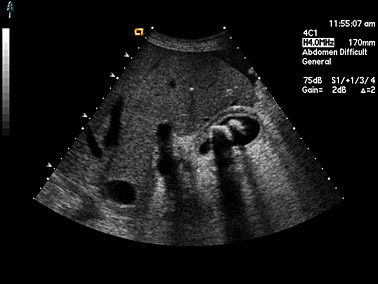

Als ergänzendes bildgebendes Verfahren kann die Ultraschalluntersuchung (Sonographie) zur Brustkrebs-Früherkennung bzw. zur Beurteilung von Knoten in der Brust eingesetzt werden.

Auch Sonographie macht innere Organe und Gefäße sichtbar. Hat bei einer Patientin die Mammographie keine eindeutige Diagnose ergeben, kann die Ultraschalluntersuchung der Brust zur Hilfe genommen werden. Dieses Untersuchungsverfahren hat den Vorteil, dass es beliebig oft wiederholt werden kann, da die Patientin keiner Strahlenbelastung ausgesetzt wird.